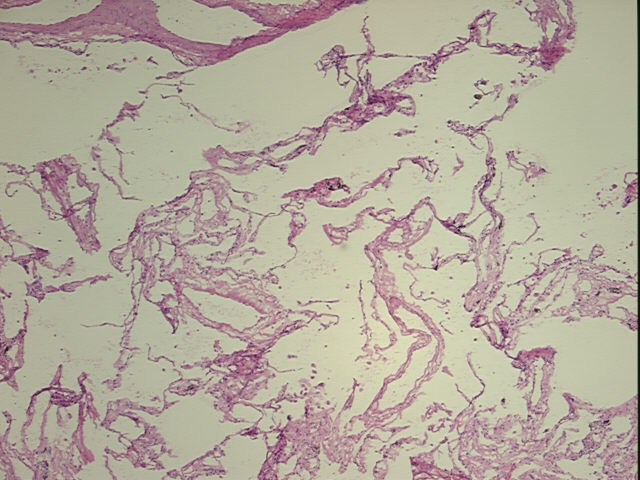

Within this product group you will find human biologicals that include normal and clinical (disease state) materials such as whole blood, plasma, serum, urine, cerebrospinal fluid, sputum, PBMCs, etc.